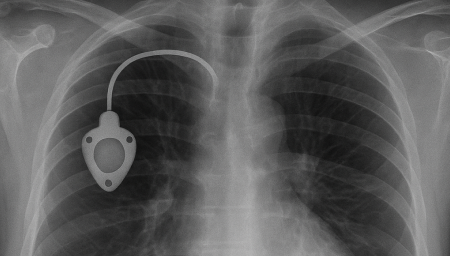

항암관(Chemoport)삽입

Chemoport는 항암제처럼 자극이 강한 약물을 안전하고 안정적으로 투여하기 위해 흉부 피부 아래에 이식하는 중심정맥 사용 포트입니다. 팔 혈관이 약하거나 반복 주사로 인한 통증이 걱정되는 환자에게 도움을 줄 수 있으며, 장기간 치료가 필요한 경우 편안하게 항암 치료를 지속할 수 있도록 설계되어 있습니다.

항암관(Chemoport)삽입 과정

국소마취 후 작은 절개를 시행 (보통 쇄골 아래 약 2~3cm 정도 절개)

정맥에 카테터 삽입 후 포트와 연결

방사선으로 카테터 위치 확인